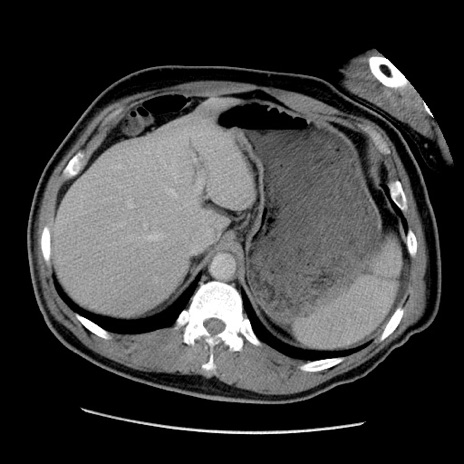

症例22(横断像)

【症例】50歳代男性

【主訴】腹痛

【現病歴】AVMからの被殻出血のため回復期リハ病棟入院中。 本日午後3時頃急に下腹部痛が出現した。

【既往歴】AVM、被殻出血、虫垂炎、高血圧

【身体所見】意識晴明、左半身不全麻痺、会話の理解は良好、36.5°C、腹部:膨隆、全体に板状硬、下腹部正中に圧痛点あり、反跳痛-、筋性防御不明、右下腹部にope scar

【データ】WBC 9400、CRP 0.06